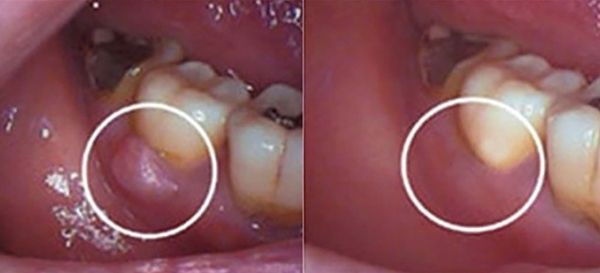

치은염은 증상이 뚜렷하게 나타나지 않아 간단한 치료만으로 회복할 수 있지만, 잇몸이 내려앉아 치아 뿌리가 노출되거나 치주인대와 잇몸뼈가 파괴되는 치주염이 진행되면 이야기가 달라진다.

치주염은 잇몸에서 피가 나고 붓거나 이가 시린 증상이 나타나는데, 이는 만성질환으로 오랫동안 서서히 진행된다. 치주염이 심해지면 건강한 잇몸으로 돌아가기가 사실상 불가능하다. 증상이 있든 없든 매일 꾸준한 구강 위생 관리가 중요한 이유다.